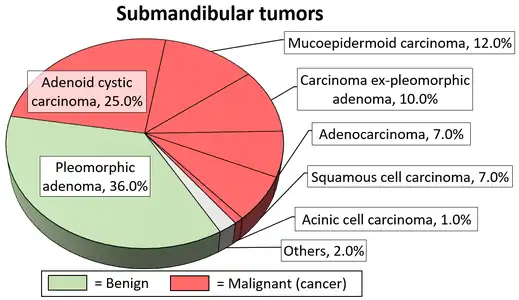

Little is known about the total incidence of salivary gland tumours as most benign tumours go unrecorded in national cancer registries.[3] The majority of salivary tumours are benign (65-70%).[4] Within the parotid gland 75 - 80% of tumours are benign. Around 50% of the tumours found in the submandibular glands are benign. Sublingual gland tumours are very rare but if present, they are most likely to be malignant.[4][19] Saku et al. in 1997 [20] and Venturi [21][22] in 2021, reported the causal role for ionizing radiation in salivary gland tumorigenesis, particularly for mucoepidermoid carcinoma.

Diagrams by Mikael Häggström - 1 2 Barnes L (23 December 2008). Surgical Pathology of the Head and Neck. Vol. 1 (3rd ed.). Taylor & Francis. p. 511. ISBN 978-0-8493-9023-4.